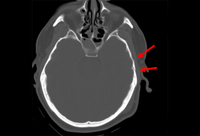

Occipital fracture extending to foramen magnum: risk of brainstem compression by hematoma

From the teaching collection of Demetrios Demetriades; used with permission